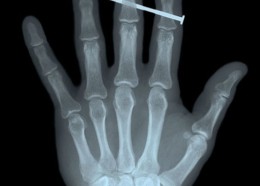

Чудни ренгенски снимки